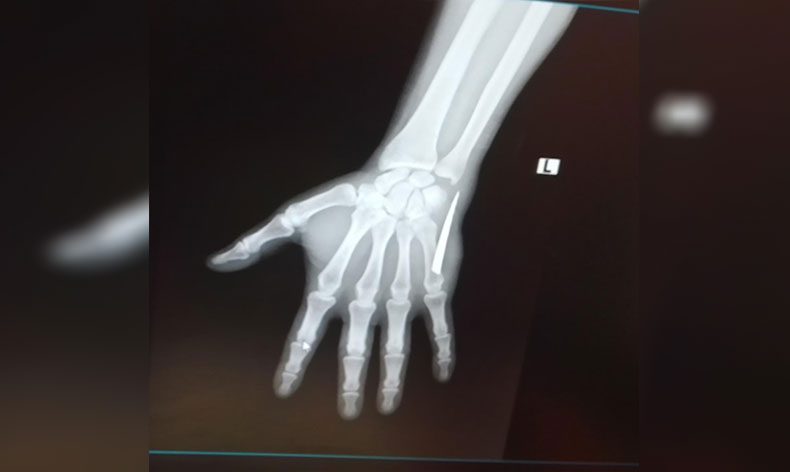

O esnada bıçak kırıldı ama parçasını göremedim. Eşimle beraber elimi sarıp Devrek Devlet Hastanesi aciline gittik. Pansuman yapacağız diye yarım saat beklettiler donra doktor Ekrem Sönmez herhangi röntgen işlem falan yapmadan elime bakıp zımba atılmasını söyledi. Kan kaybettiğim için kimse dokunamadı. Doktor Ekrem bey kendisi zımba attı. Sonrasında elimi sardılar, beni eve gönderdiler. Aradan geçen zaman zarfında dikiş yerlerim iyileşmeye başladı fakat bir yerinde yara oluştu. Sürekli kanama yapmaya başladı. Bu sebepten ötürü birkaç defa hastaneye gittiğimde pansuman yapıp gönderdiler. Film çekilmesini istedim, ‘Kırık, çıkık için film çekilir bu kadar yara için film çekilmez’ dediler. 28 Kasım Pazartesi günü daha şiddetli bir ağrıyla uyandım. Elime baktığımda bir parça olduğunu hissettim. Küçük bir parça sandım eşimle almaya çalıştık ama baya büyük olduğunu fark ettik. Bunun üzerine Çaycuma Devlet Hastanesi’ne geldik. Hemen röntgen çekildi ve elimdeki parçanın baya büyük olduğu söylenildi. Sonrasında ameliyat ile bıçağın parçasını aldılar.”

5 santimetrelik bıçak parçasının yaşattığı acı nedeniyle elini kullanamadığını ve dolayısıyla da iki ay boyunca çalışamadığını söyleyen Köseli, “Parmakta uyuşma, ağrı yapıyordu. Koluma engel olmaya başlamıştı. Güç kaybı da yaşayınca işsiz kaldım. Elimdeki bıçak parçası yüzünden hem elimden oluyordum hem de işsiz kaldım. Elim sürekli sargı içindeydi ve sürekli kanama yaşıyordum. Sargıyı çıkardığım zaman kanamam aşırı derecede artıyordu. Kan kaybı yüzünden kan oranlarımda da düşüklük çıktı. Kanama olmasına rağmen iyice temizlemeye çalıştım. O esnada elimin içinde bir şey olduğunu fark ettim. Elimle dışarıdan doğru ittirmeye başladım. Yüzeye doğru parça geldi. Korkutan gerçek, Çaycuma Devlet Hastanesi’ne gelince meydana çıktı. Çıkan parçada gördünüz gibi büyük ve tırtıklı bir bıçak. Tırtıklı bıçak normal bıçak yüzüne göre daha zararlı. Kolumda da baya hasar oluşturdu” dedi.